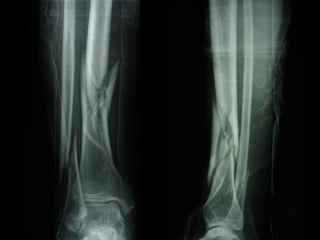

Dal Gennaio 2000 al Febbraio 2006 abbiamo trattato 167 fratture chiuse  con placca percutanea  in 164 pazienti :  27 lesioni diafisarie di gamba, 12 piloni tibiali ,  11 fratture prossimali di tibia, 36 fratture sovracondiloidee di femore, 17 fratture diafisarie di femore, 43 fratture metaepifisarie prossimali di omero, 21 diafisarie d’omero.  156 guarigioni 8 fallimenti

I buoni risultati ottenuti dipendono da 5 punti fondamentali:   una accurata riduzione percutanea della frattura  precise vie di accesso  l’utilizzo della placca che consenta il più lungo braccio di leva possibile il pretensionamento della placca  una sintesi con un ridotto numero di viti

Accurata riduzione percutanea della frattura

Precise vie di accesso

Placche lunghe e pretensionate

Placche lunghe e pretensionate Sintesi con un ridotto numero di viti